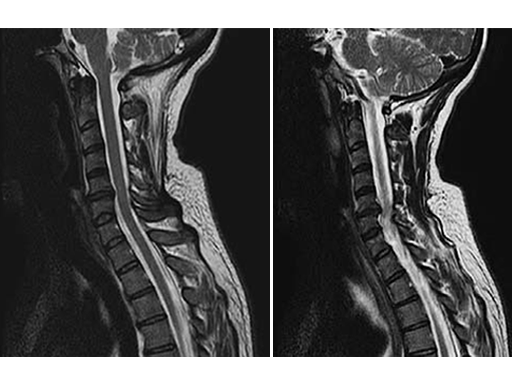

A 49-year-old woman complained of a persistent cervicobrachial pain syndrome on the right side, over a period of five years, which was refractory to all conservative treatments. The conventional x-ray of the cervical spine showed a slightly pronounced degeneration with kyphosis of the segment C5/6, and preoperative MRI showed disc protusion (fig.1).